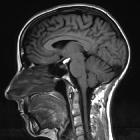

Osteolipomas are usually in the suprasellar and interpeduncular cistern, close to the pituitary infundibulum, inferior surface of the hypothalamus, mammillary bodies and tuber cinereum .

Central fat signal that attenuates on fat-saturated sequences is surrounded by calcification which results in low signal on most sequences and blooming on T2*/SWI sequences .

No enhancing component is helpful in distinguishing osteolipomas from tumors such as teratomas or craniopharyngiomas.